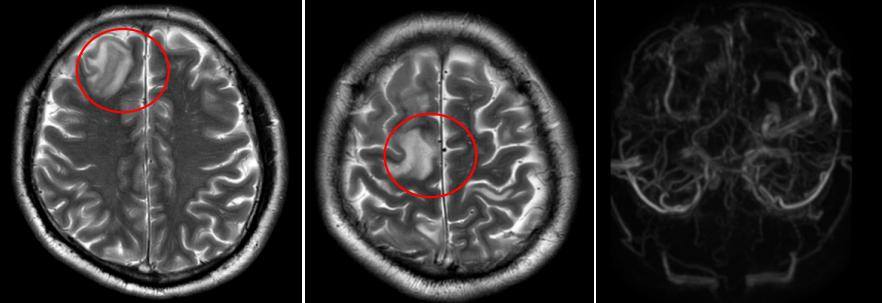

该院神经内二科陈婉洁医生接诊患者后,通过详细问诊和查体,高度怀疑静脉窦血栓形成。在科室主任钟水生指导下,紧急安排了相关检查。头颅磁共振检查显示:右侧颈内静脉、双侧乙状窦、横窦、窦汇、上矢状窦多发血栓,伴静脉淤积性脑梗死。

患者头颅磁共振检查